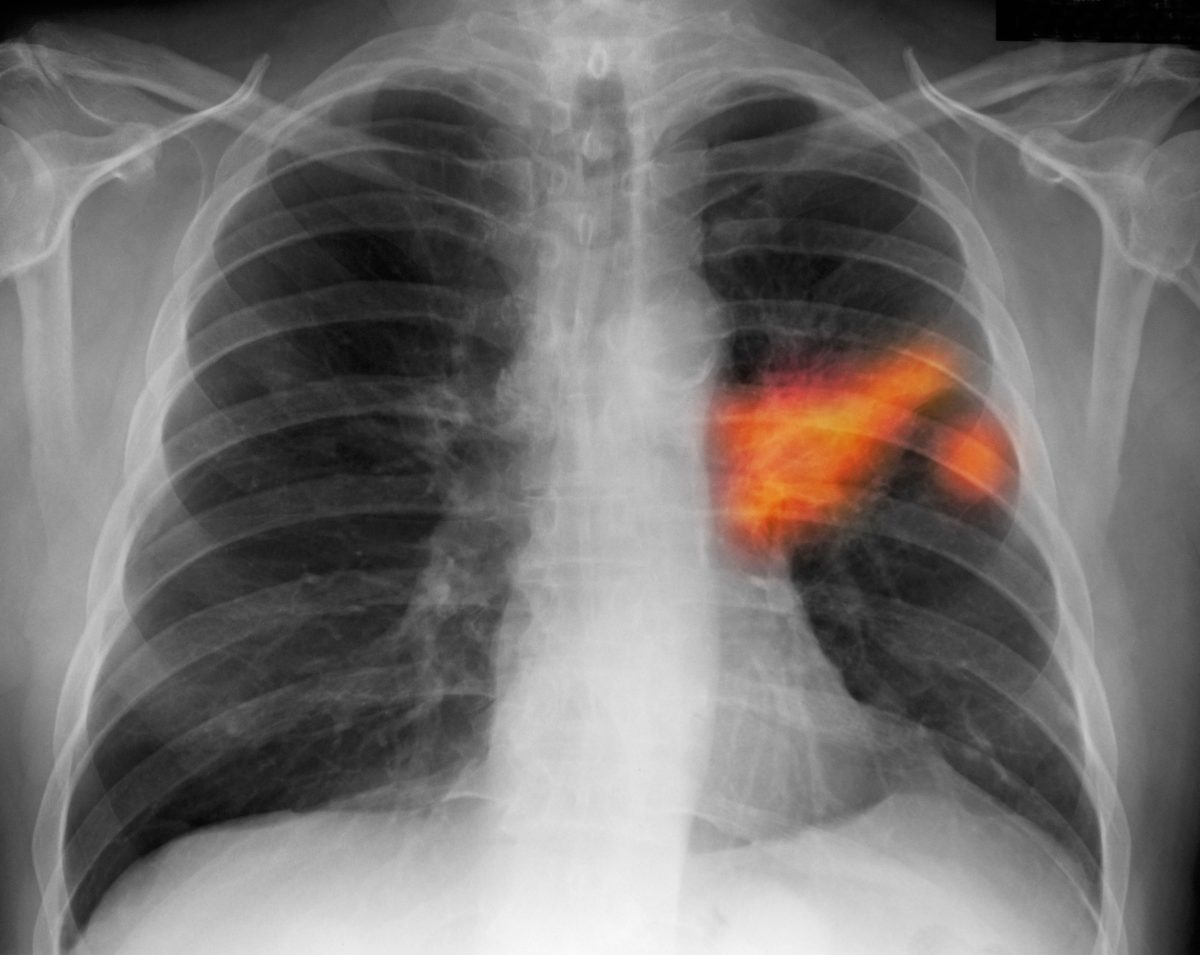

Ogni anno in Italia si registrano quarantamila nuove diagnosi di tumore al polmone e trentaquattromila decessi. Nell’ottanta per cento dei casi il tumore è provocato dal fumo di sigaretta: per questi pazienti, fino ad oggi, l’unica arma a disposizione era la chemioterapia, tossica e poco efficace: la sopravvivenza in fase avanzata, con questa cura, non supera i 10 mesi.

L’introduzione dell’immunoterapia ha cambiato lo scenario: un paziente su cinque a tre anni dalla diagnosi è vivo. E funziona bene soprattutto nei grandi fumatori e negli ex fumatori.

L’obiettivo dell’immunoncologia è quello di combattere il tumore stimolando il sistema immunitario del paziente e scagliandolo contro la malattia. Dopo il melanoma, il cancro polmonare è il primo tumore solido trattabile con questo metodo. Da tempo si provava a scatenare il sistema immunitario del paziente contro le cellule neoplastiche, ma senza successo. Dopo cinquant’anni di sperimentazioni, passando anche per l’insuccesso del vaccino, abbiamo capito finalmente il meccanismo per aggredire il tumore: usare anticorpi monoclonali che rimuovono il blocco che il tumore stesso crea contro il sistema immunitario. Quest’ultimo è così in grado di contrastare la neoplasia. Ci sono farmaci specifici, come nivolumab, che agiscono proprio in questo modo.

L’aspettativa di vita per un tumore al IV stadio è passata dai sette-otto mesi garantiti dalla chemioterapia fino a due anni su un paziente su quattro.

Abbiamo visto che l’immunoterapia è particolarmente efficace nel tumore squamoso non a piccole cellule, quello tipico dei forti fumatori. Ma c’è un 20 per cento dei casi in cui il tumore è invece legato ad una mutazione genetica e in questo caso il trattamento non funziona. Ma per questo tipo di cancro ci si può avvalere dei farmaci biologici a bersaglio molecolare, altra recente rivoluzione che ha portato a grandi successi. Inoltre il paziente, per essere candidabile, non deve avere malattie autoimmuni, come per esempio il lupus o l’artrite reumatoide. Ad oggi circa duemila persone l’anno vengono sottoposte a immunoterapia, specialmente quando falliscono il primo ciclo di chemio.